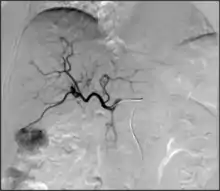

- Angiography: Imaging the blood vessels to look for abnormalities with the use of various contrast media, including iodinated contrast, gadolinium based agents, and CO2 gas.[3]

- Angiography: Sometimes referred to as traditional angiography, catheter angiography or digital subtraction angiography (DSA.) A small needle is inserted into a blood vessel, then exchanged for a catheter over a wire. The catheter is directed at the vessel to be studied, and contrast is directly injected to evaluate the lumen under video X-ray. This is an older technique than modern CT Angiography or MR Angiography, but provides unique advantages. With a catheter in place, provocative maneuvers can be performed such as breath holds or instillation of vasodilators, to evaluate a patient's blood flow dynamically. This can reproduce symptoms and identify functional abnormalities in a vessel that a static CT or MR imaging cannot.[79][80] Angiography provides the basis for all endovascular therapy.